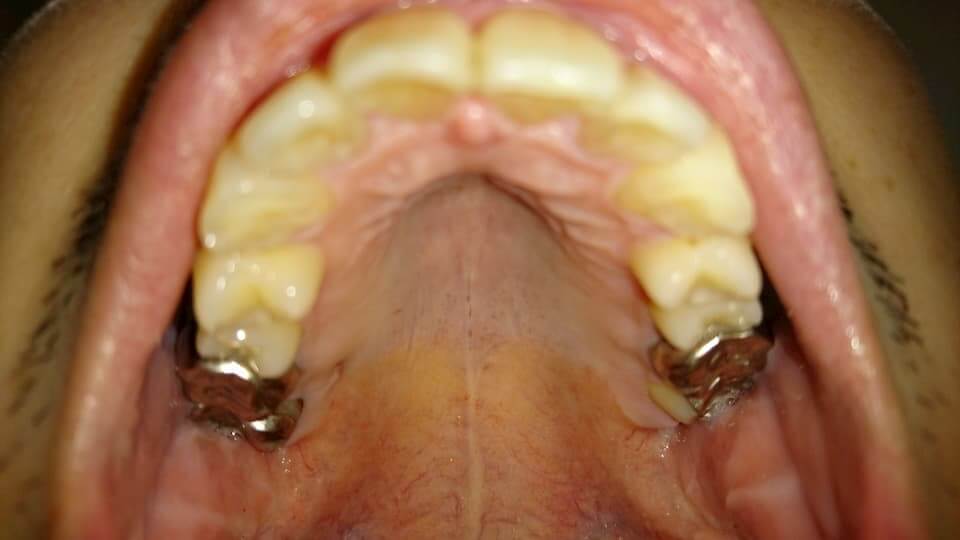

歯の写真